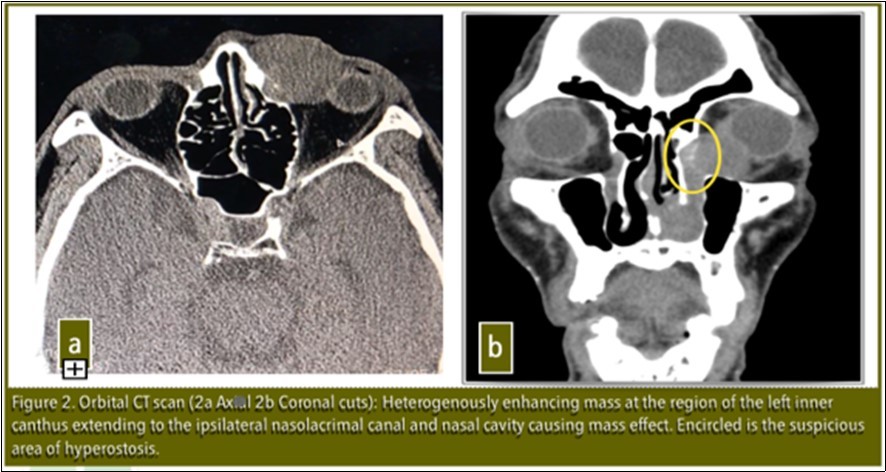

Visual acuity, slit lamp examination, extraocular eye muscle movements were unremarkable at the time of examination except for lacrimal apparatus irrigation which showed blockage at the level of the left common canaliculus. Orbital CT-scan revealed: Heterogenously enhancing mass extending to ipsilateral nasolacrimal canal and nasal cavity causing mass effect. No bone erosions present. There was note of a suspicious area of hyperostosis in the area of the lacrimal sac [Figure 2]. Patient was referred to the Department of Otolaryngology Head and Neck Surgery for co-management. Punch biopsy was done and histopathology revealed Inverting Papilloma.

Figure 2.Orbital CT scan ( 2a Axial. 2b Coronal cuts): Heterogenously enhancing mass at the region of the left inner canthus extending to the ipsilateral nasolacrimal canal and nasal cavity causing mass effect. Encircled is the suspicious area of hyperostosis.

It is important to determine the area of origin by CT scan to optimize the proper surgical management and prevent recurrence.3Lee et al in his paper in 2007 noted that there is a high correlation between the origin of the inverted papilloma and focal hyperostosis on CT scan which might facilitate prediction of tumor origin.3

In our patient, hyperostosis was noted in the area of the lacrimal sac on CT scan which was clinically correlated intraoperatively with adhesion of the mass to the bone in the lacrimal sac. This is further evidence that the origin of this tumor is in the lacrimal sac.